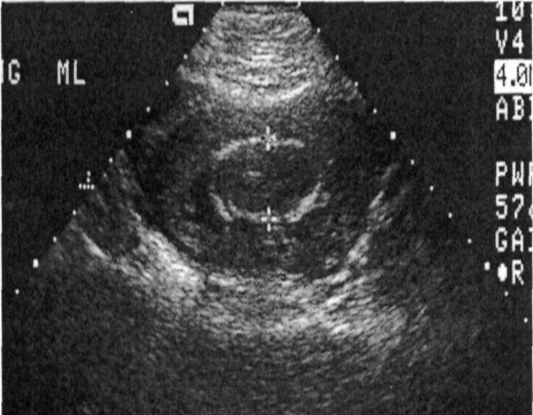

Monochorionic/diamniotic twin gestation